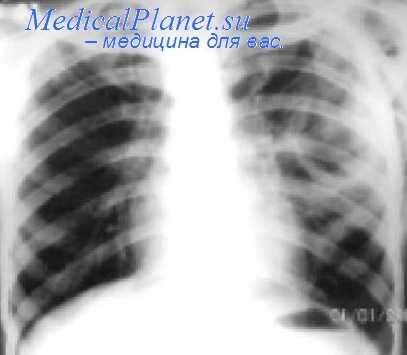

В 1910—1913 гг. Якобеус (Н. Jacobeus, 1915) сконструировал торакоскоп и разработал операцию закрытого пережигания плевральных сращений. Первое время торакокаустика сопровождалась значительным количеством осложнений, главными из которых были кровотечения и повреждения легочной ткани. После детального морфологического изучения плевральных сращений, уточнения показаний к операции, улучшения инструментария и усовершенствования хирургической техники торакокаустика стала получать все большее распространение.

В СССР первую торакокаустику произвел М. П. Уманский в 1929 г. (по Н. В. Антелаве, 1952). С 1929 г. эту операцию стал широко применять К. Д. Есипов (1933). Для разработки, усовершенствования и пропаганды пережигания сращений особенно много сделал Н. Г. Стойко. За короткий срок торакокаустика была освоена десятками хирургов и фтизиатров нашей страны. Она стала самой распространенной операцией при туберкулезе легких, без которой искусственный пневмоторакс теряет половину своей ценности (Н. Г. Стойко, 1937).

Из всех методов К. наибольшее значение приобрел искусственный пневмоторакс. До появления специфических противотуберкулезных химиопрепаратов он был основным методом лечения различных форм легочного туберкулеза. Его роль особенно возросла после разработки Якобеусом (H. Ch. Jacobaeus, 1913) метода закрытого пережигания плевральных сращений гальванокаутером. Л. К. Богуш (1945) широко применял гидравлическую препаровку плевральных сращений, вдвое увеличивающую эффективность операции Якобеуса.